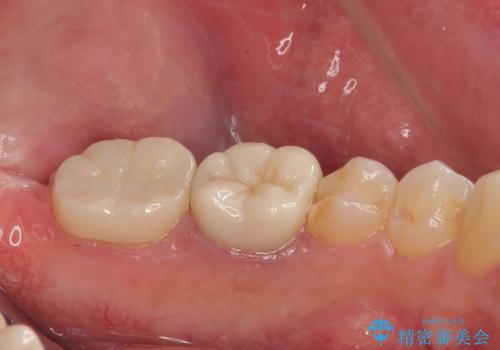

詰め物の範囲が大きいためフルジルコニアクラウンによる補綴治療を行いました。

審美面、機能面ともに満足していただけました。

咬み合わせが強い方なので夜間にマウスピースを使ってもらいながら、メインテナンスで通ってもらう予定です。